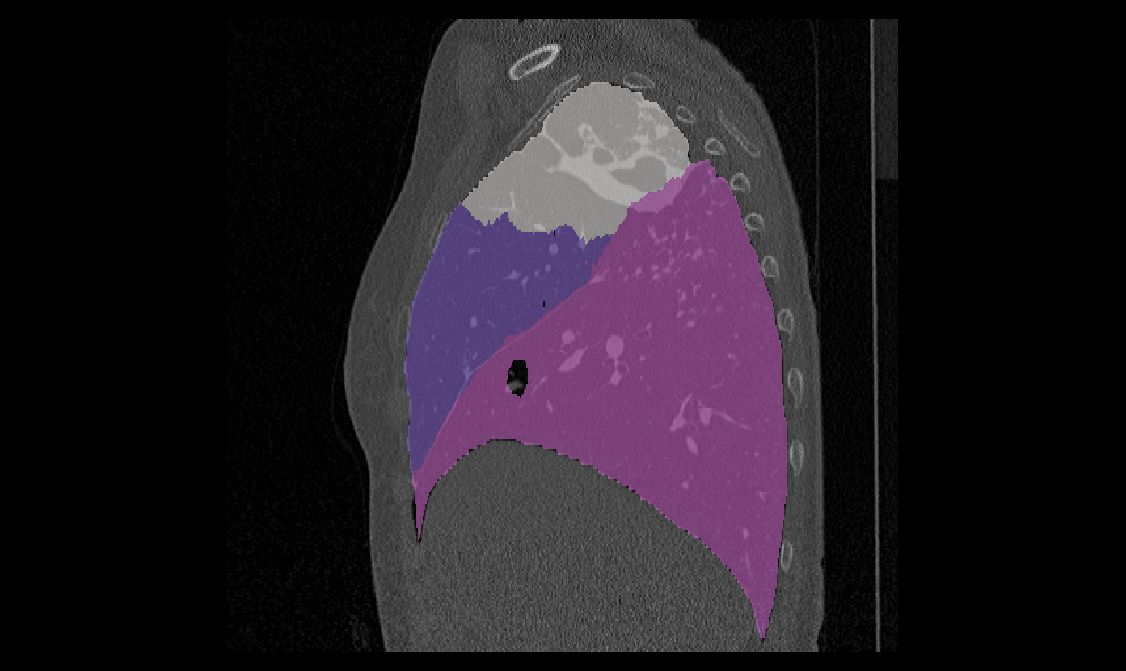

(1) Brain MR (2) Liver MR (3) Liver CT (4) Lung CT

We first introduce a method for connecting the output of a CNN to an ACM, yielding a model for the precise delineation of lesions, to which we refer as Deep Active Lesion Segmentation (DALS) (Figure 4). We then go further to introduce a truly unified framework (Figure 5) that bridges the gap between ACMs and CNNs by leveraging a novel, automatically differentiable level-set ACM with trainable parameters that allows for back-propagation of gradients and can be end-to-end trained along with a backbone CNN from scratch, without any CNN pre-training. The ACM is initialized directly by the CNN and utilizes an energy functional that is locally-tunable by the backbone CNN, through 2D feature maps. Thus, our work overcomes the big hurdle of fully automating the powerful ACM approach to image segmentation. We have applied our proposed framework to the task of building segmentation in aerial images (Figure 6).

Deep Active Lesion Segmentation

[45]: Lesion segmentation is an important problem in computer-assisted diagnosis that remains challenging due to the prevalence of low contrast, irregular boundaries that are unamenable to shape priors. We introduce Deep Active Lesion Segmentation (DALS), a fully automated segmentation framework that leverages the powerful nonlinear feature extraction abilities of FCNs and the precise boundary delineation abilities of ACMs. Our DALS framework benefits from an improved level-set ACM formulation with a per-pixel-parameterized energy functional and a novel multiscale encoder-decoder CNN that learns an initialization probability map along with parameter maps for the ACM. We evaluate our lesion segmentation model on a new Multiorgan Lesion Segmentation (MLS) dataset that contains images of various organs, including brain, liver, and lung, across different imaging modalities—MR and CT. Our results demonstrate favorable performance compared to competing methods, especially for small training datasets. -